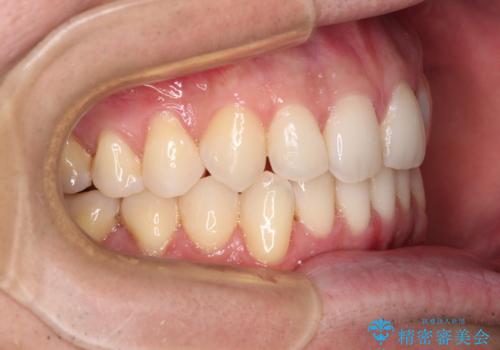

ディープバイトと叢生 インビザラインによる矯正治療

- 前歯のディープバイトと叢生を気にして来院された患者様です。

目立ちにくい装置を希望されていたため、ワイヤー装置とインビザラインを提案したところ、インビザラインを希望されました。

上下ともに叢生が認められたため、親知らずすべてを抜歯し、歯列全体を後方へ移動させることで歯列を整えることとしました。

上顎奥歯の銀歯も気になっていたので、矯正治療の途中でセラミッククラウンへ変更し、その後歯列を仕上げていくこととしました。

ディープバイトもデコボコも改善され、気になっていた銀歯もセラミックとなり、患者様には大変満足していただきました。